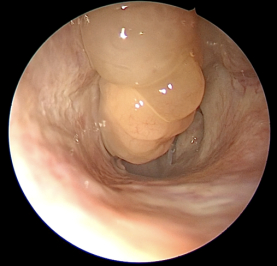

鼻息肉是长在鼻腔里的外表似荔枝肉样的光滑肿块,它并非肿瘤性新生物,而是鼻腔鼻窦过度炎症水肿的产物。单纯的鼻息肉较少见,常见的是慢性鼻-鼻窦炎伴有鼻息肉,且多发于双侧。

常常有人把下鼻甲(鼻腔的正常结构)误认为是鼻息肉,因为大家在照镜子时很容易观察到这个结构,而且发现有时候“这块肉”变红变大了,因此来院就诊。一般来说,观察鼻息肉需要借助医用工具,如前鼻镜或鼻内镜,否则很难被观察到。除非鼻息肉非常大、向前突出到鼻孔部位。

通过鼻内镜检查,刘教授观察到,陈先生上呼吸道双侧鼻腔中鼻道、嗅裂有鼻息肉,软腭平面和舌根平面没有明显狭窄。同时,鼻窦CT显示,陈先生患有双侧鼻窦炎。